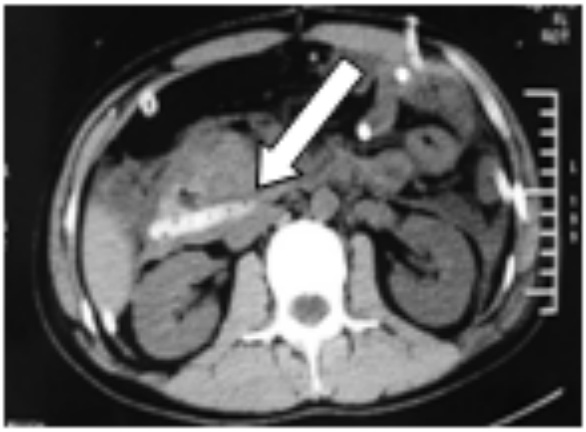

图 3 粗箭头提示胰尾积液基本吸收,细箭头为穿刺管位置